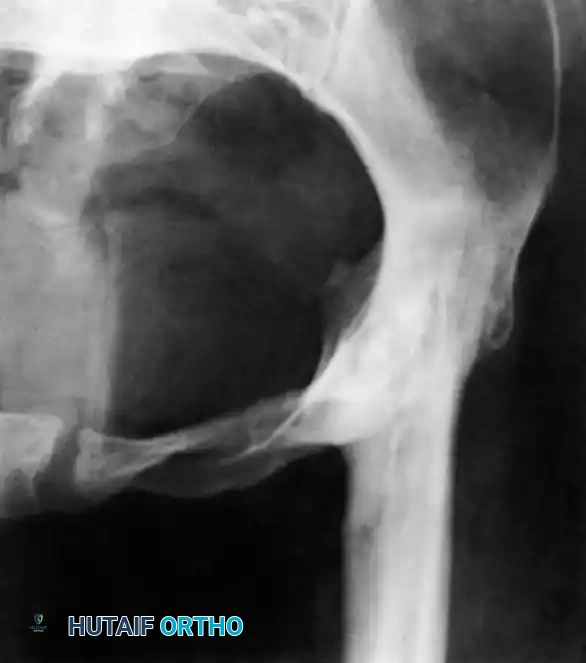

The Hip and Pelvis

Tuberculosis of the hip frequently affects children and young adults. The disease begins in the acetabular roof or the femoral head, rapidly progressing to joint space narrowing and severe destruction. A classic late-stage presentation is the "wandering acetabulum," where superior and medial migration of the femoral head occurs due to progressive bone loss.

In cases of severe destruction, nonoperative management leads to painful, fibrous ankylosis in a non-functional position (flexion, adduction, and internal rotation). Surgical intervention involves radical debridement. In modern practice, a two-stage total hip arthroplasty (THA) is often favored over hip arthrodesis to maintain mobility, provided the infection is medically cleared.